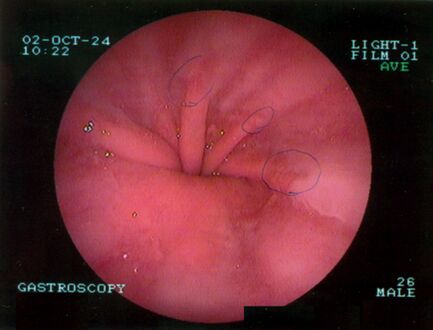

تنظير الجهاز الهضمي العلوي في وضع الانثناء للخلف يظهر الفتق الحجابي من النوع الأول.